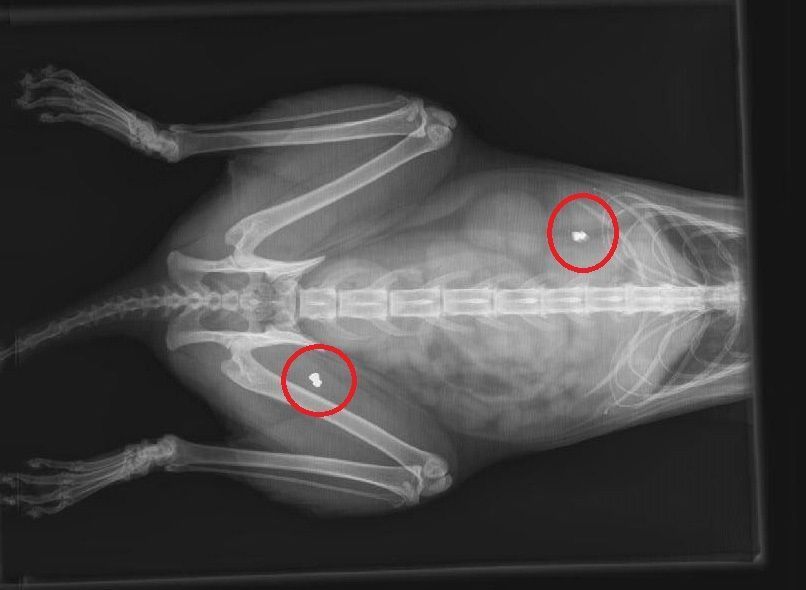

4) Βίκτωρας: Βρέθηκε στις 9 Ιανουαρίου 2016 στην οδό Νάξου και Κερκύρας στο Γαλάτσι με σπασμένο σαγόνι. Ωστόσο στην ακτινογραφία που του έγινε διαπιστώθηκε ότι πριν, είχε πυροβοληθεί στην αριστερή ωμοπλάτη. Το γατί ακόμα νοσηλεύεται και έχει κάνει χειρουργείο για το σπασμένο σαγόνι του. Το σφαιρίδιο ούτε σε αυτή την περίπτωση μπορεί να αφαιρεθεί.

GalatsiPyrovolimenosVictoras2016 (3)Το σφαιρίδιο στο κορμί του Βίκτωρα έδειξε η ακτινογραφία.